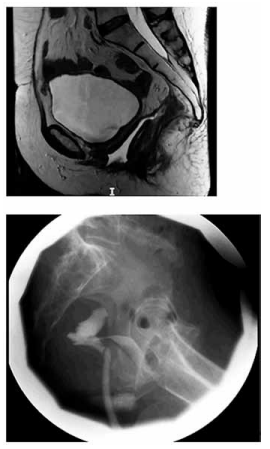

Paciente de 42 anos foi submetida a histerectomia total

e retossigmoidectomia laparoscópica com anastomose

mecânica por endometriose profunda. No terceiro dia de

pós-operatório, apresenta descarga de conteúdo fétido

pela vagina. Foi realizado estudo radiológico, apresentado a seguir:

(Arquivo pessoal; imagem usada com autorização)

Com base nas imagens e na cronologia do caso, qual é a causa mais provável dessa complicação?